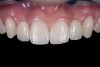

(2.) After orthodontic alignment of teeth and bleaching. Note alveolar deficiency in right lateral incisor site and diminutive left lateral incisor.

Figure 2

A 14-year-old patient presented to the office with his mother (Figure 1). His chief complaint involved the large spaces between the teeth created by his missing right maxillary lateral incisor and his small left maxillary lateral incisor. He desired to replace the missing tooth with an implant and create a beautiful smile. Upon examination, he was found to have a class I canine and molar relationship, but because he had a tooth size/arch size discrepancy and space distal to the right central incisor, the remaining incisors had drifted to the right. The left maxillary lateral incisor was peg-shaped and in a cross bite position. Studies have shown a clear association between congenitally missing teeth and reduced tooth size.59-62 Because he was only 14-years-old at the time and could not have implants placed until the cessation of growth (somewhere in the vicinity of 22 years old), he was sent to the orthodontist for alignment of the teeth.16,17 After 2 years of orthodontics, the appliances were removed, and his tooth coloration was improved using carbamide peroxide bleaching (Figure 2). Because some form of provisional needed to be placed until he was finished growing, a double-wing metal resin-bonded bridge was chosen. As discussed earlier, this is the ideal transitional prosthesis for patients that have congenitally missing maxillary lateral incisors. The benefits of this type of prosthesis include its ability to be removed and rebonded during the surgical phase of treatment and its ability to retain the roots in their proper position after orthodontic treatment.16 The final plan for the patient was to increase the width of the central and the maxillary left lateral incisor, utilizing porcelain laminate veneers to achieve the appropriate width/length ratio of 80%. A wax-up was created to idealize tooth size, a putty matrix was made from the wax-up to facilitate bonding of the incisors, and a non-precious, double-wing metal resin-bonded bridge was fabricated for lateral incisor replacement. Once the teeth were bonded to ideal size, the “Maryland Bridge” was fabricated from a polyvinyl arch impression with the newly bonded teeth (Figure 3). The metal frame was cast from a non-precious alloy to allow for fabrication of a very thin frame and to create a better surface for bonding. After sandblasting the internal aspect of the frame with CoJet™ silica (3M ESPE), accomplishing salinization, and executing cementation with a dual-cure resin cement, a fairly good adhesion to the frame was anticipated.29 The enamel surface was etched with phosphoric acid for 30 seconds, the primer (Single Bond Plus, 3M ESPE) was applied to both the internal surface of the sandblasted framework and the etched enamel, and the bridge was cemented with RelyX™ ARC (3M Espe) dual-cured resin cement (Figure 4 and Figure 5).